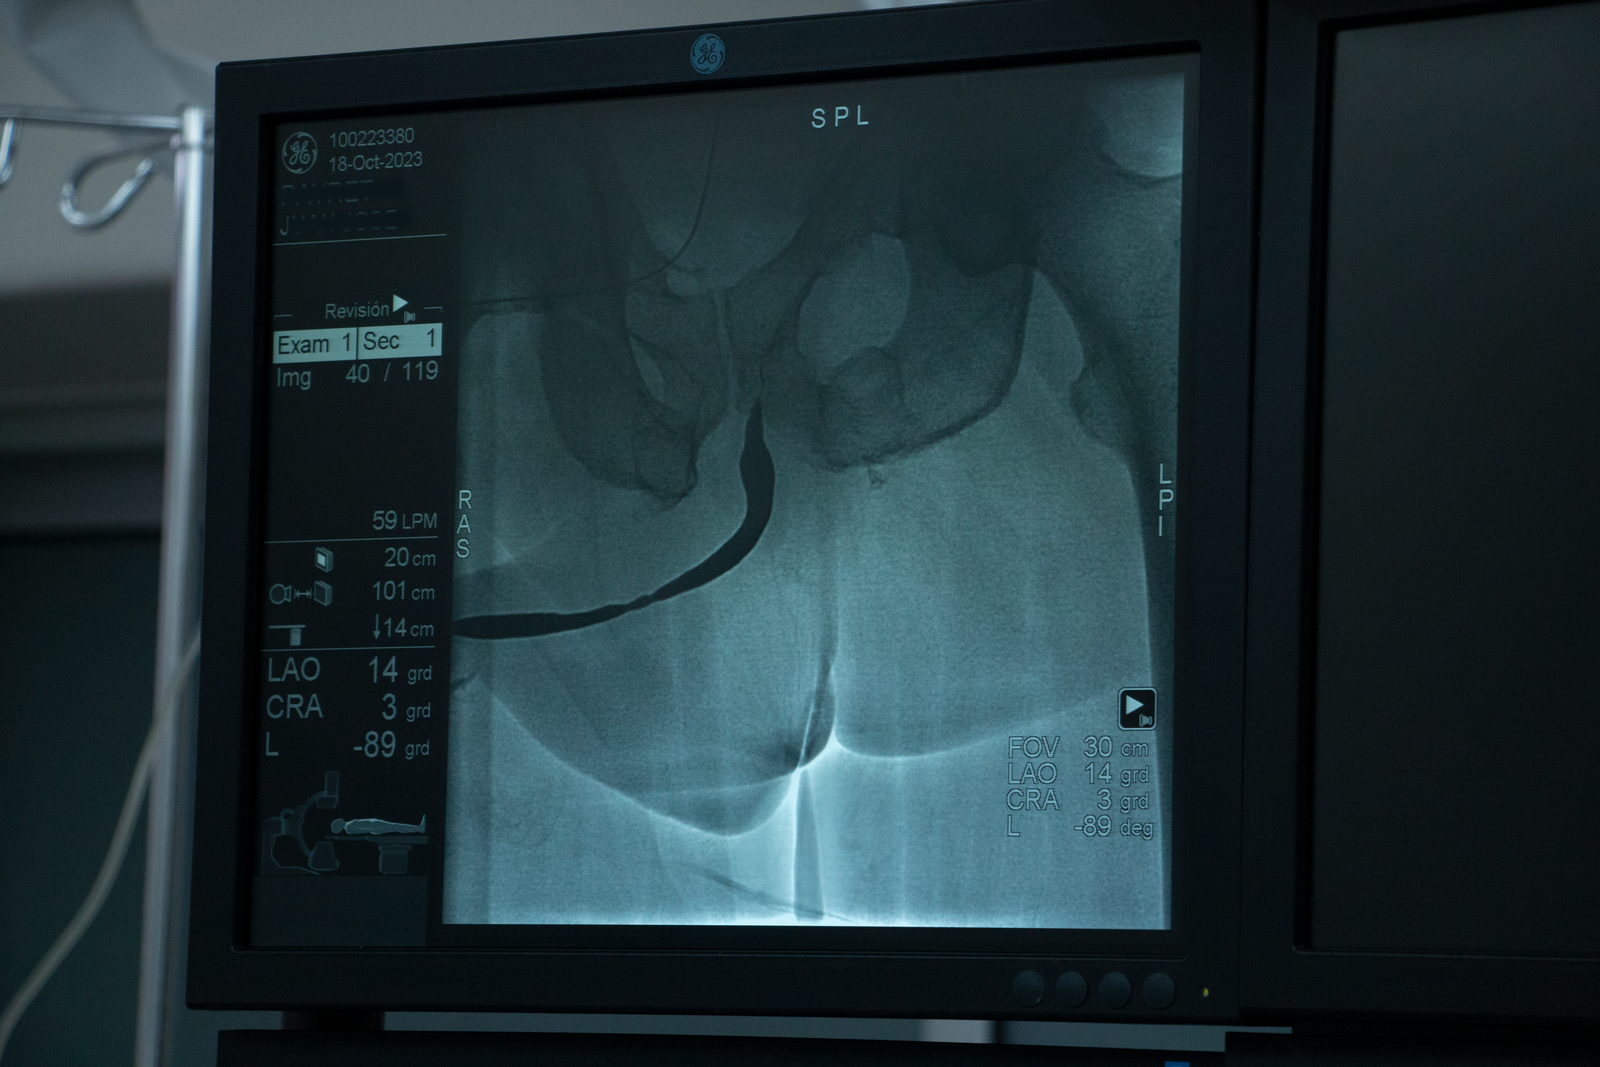

Uretroplastía procedimiento combinado mini Uretrotomía interna cutting balloon balón con paclitaxel